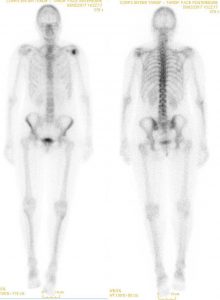

Mais qu’est ce que cela donne en Médecine Nucléaire?

Comme vous le voyez, l’IA à tendance a retrouver des patterns animalier au sein des images de scintigraphie osseuse.

A noter que l’intérêt diagnostique de telles images reste à démontrer.